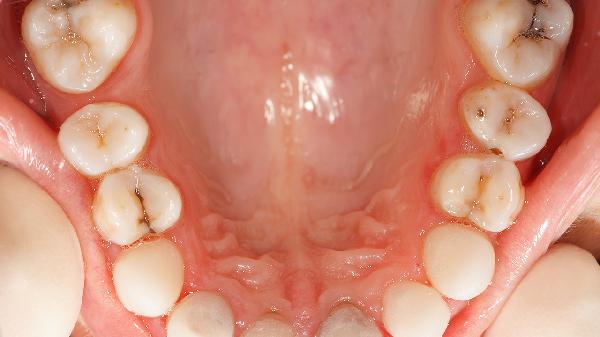

牙齿两边的肉肿起来怎么回事

牙齿两边的肉肿起来可能由牙龈炎、牙周炎、智齿冠周炎、口腔溃疡、外伤等因素引起,可通过口腔清洁、药物治疗、局部处理、饮食调整、就医检查等方式缓解。

牙龈炎是牙龈组织的炎症反应,主要由牙菌斑堆积刺激牙龈导致。表现为牙龈红肿、触碰易出血。日常需加强刷牙和牙线使用,定期洗牙清除牙结石。严重时可使用复方氯己定含漱液或甲硝唑片控制感染。

牙周炎是牙龈炎发展至牙周组织的慢性炎症,与牙菌斑中的厌氧菌感染相关。除牙龈肿痛外,常伴随牙齿松动、口臭。需进行龈下刮治等专业治疗,配合使用盐酸米诺环素软膏等局部药物。

阻生智齿周围软组织发炎称为冠周炎,多因智齿萌出空间不足导致食物嵌塞引发感染。急性期会出现张口受限、颌面部肿胀。需用生理盐水冲洗盲袋,必要时口服头孢克肟分散片联合甲硝唑抗感染。

口腔黏膜破损形成的溃疡可能波及牙龈,表现为边缘红肿的圆形创面。与免疫力下降、维生素缺乏有关。可使用西瓜霜喷剂促进愈合,避免进食辛辣刺激食物,保证充足睡眠。

硬物戳刺、刷牙力度过大等机械损伤会造成牙龈局部充血肿胀。需暂停使用患侧咀嚼,用冰敷缓解肿痛。若持续出血或出现化脓需排除牙根折裂可能。

日常应注意选择软毛牙刷采用巴氏刷牙法,每日使用牙线清洁牙缝。饮食上多摄入富含维生素C的猕猴桃、西兰花等食物,避免过烫过硬饮食刺激牙龈。肿胀持续超过3天或伴随发热、淋巴结肿大时,需及时到口腔科进行牙周探诊、X线片等检查,排除颌骨囊肿等器质性疾病。养成每年洗牙1-2次的习惯,妊娠期、糖尿病患者更需加强口腔护理。